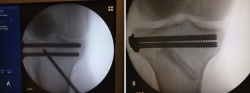

En este caso, es esencial observar las Rx con y sin tracción que nos indican cómo se va a comportar la fractura. Si la fractura es reductible en tracción, es muy probable que podamos realizar una osteosíntesis con restitución completa de la superficie articular. Al realizar la TC, apreciamos la disposición de los fragmentos para marcar una estrategia de reducción bajo control radioscópico y artroscópico, y colocación de los tornillos canulados que fijarán la epífisis distal de la tibia.

Posteriormente, colocaremos la placa en la tibia por vía MIPO realizando una incisión interna, separando la vena safena y deslizando la placa que se fija de manera provisional. Tras comprobar por radioscopia la buena posición del implante, se realiza la fijación definitiva con los tornillos que consideremos adecuados. En el caso de que tengamos que usar un fijador, este sustituye a la placa interna (Figuras 17 a 20).

Figura 17. Caso 3: fractura tipo C. Radiografías sin tracción y con tracción comprobando la reducción.

Figura 18. La tomografía computarizada muestra los fragmentos principales de la fractura, estando desplazado el Tillaux que se reduce con la tracción.

Figura 19. Colocación del tornillo en el Tillaux con la extremidad en tracción y posteriormente la placa MIPO (minimally invasive plate osteosynthesis).